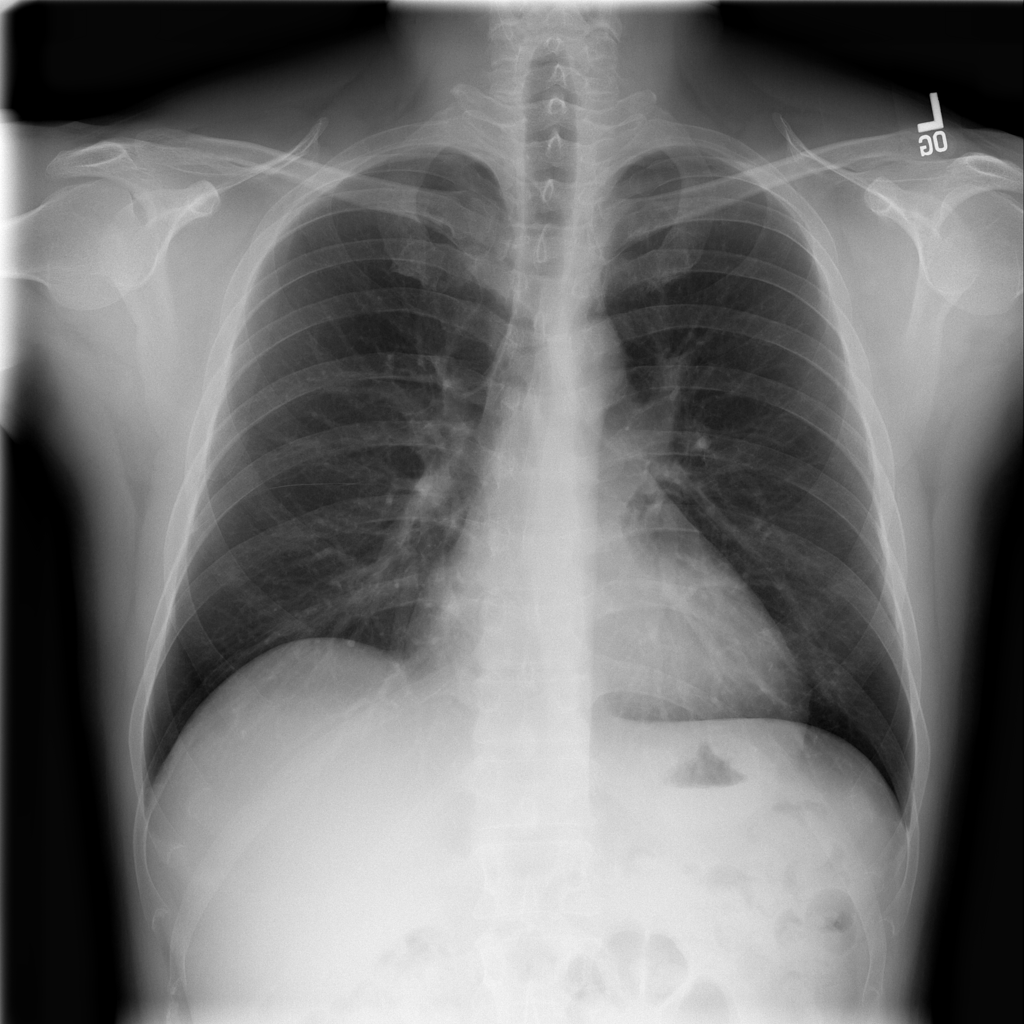

PAT-F3E7 · IMG-000Cardiomegaly

PAT-F3E7 · IMG-000

PA